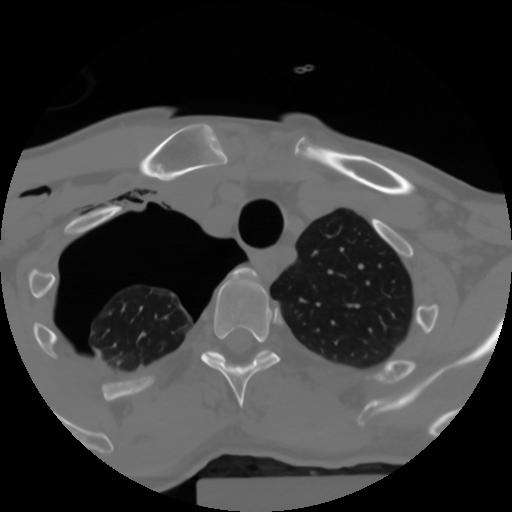

10 P.BLANDAS,,Axial,2.0,P.BLANDAS,,